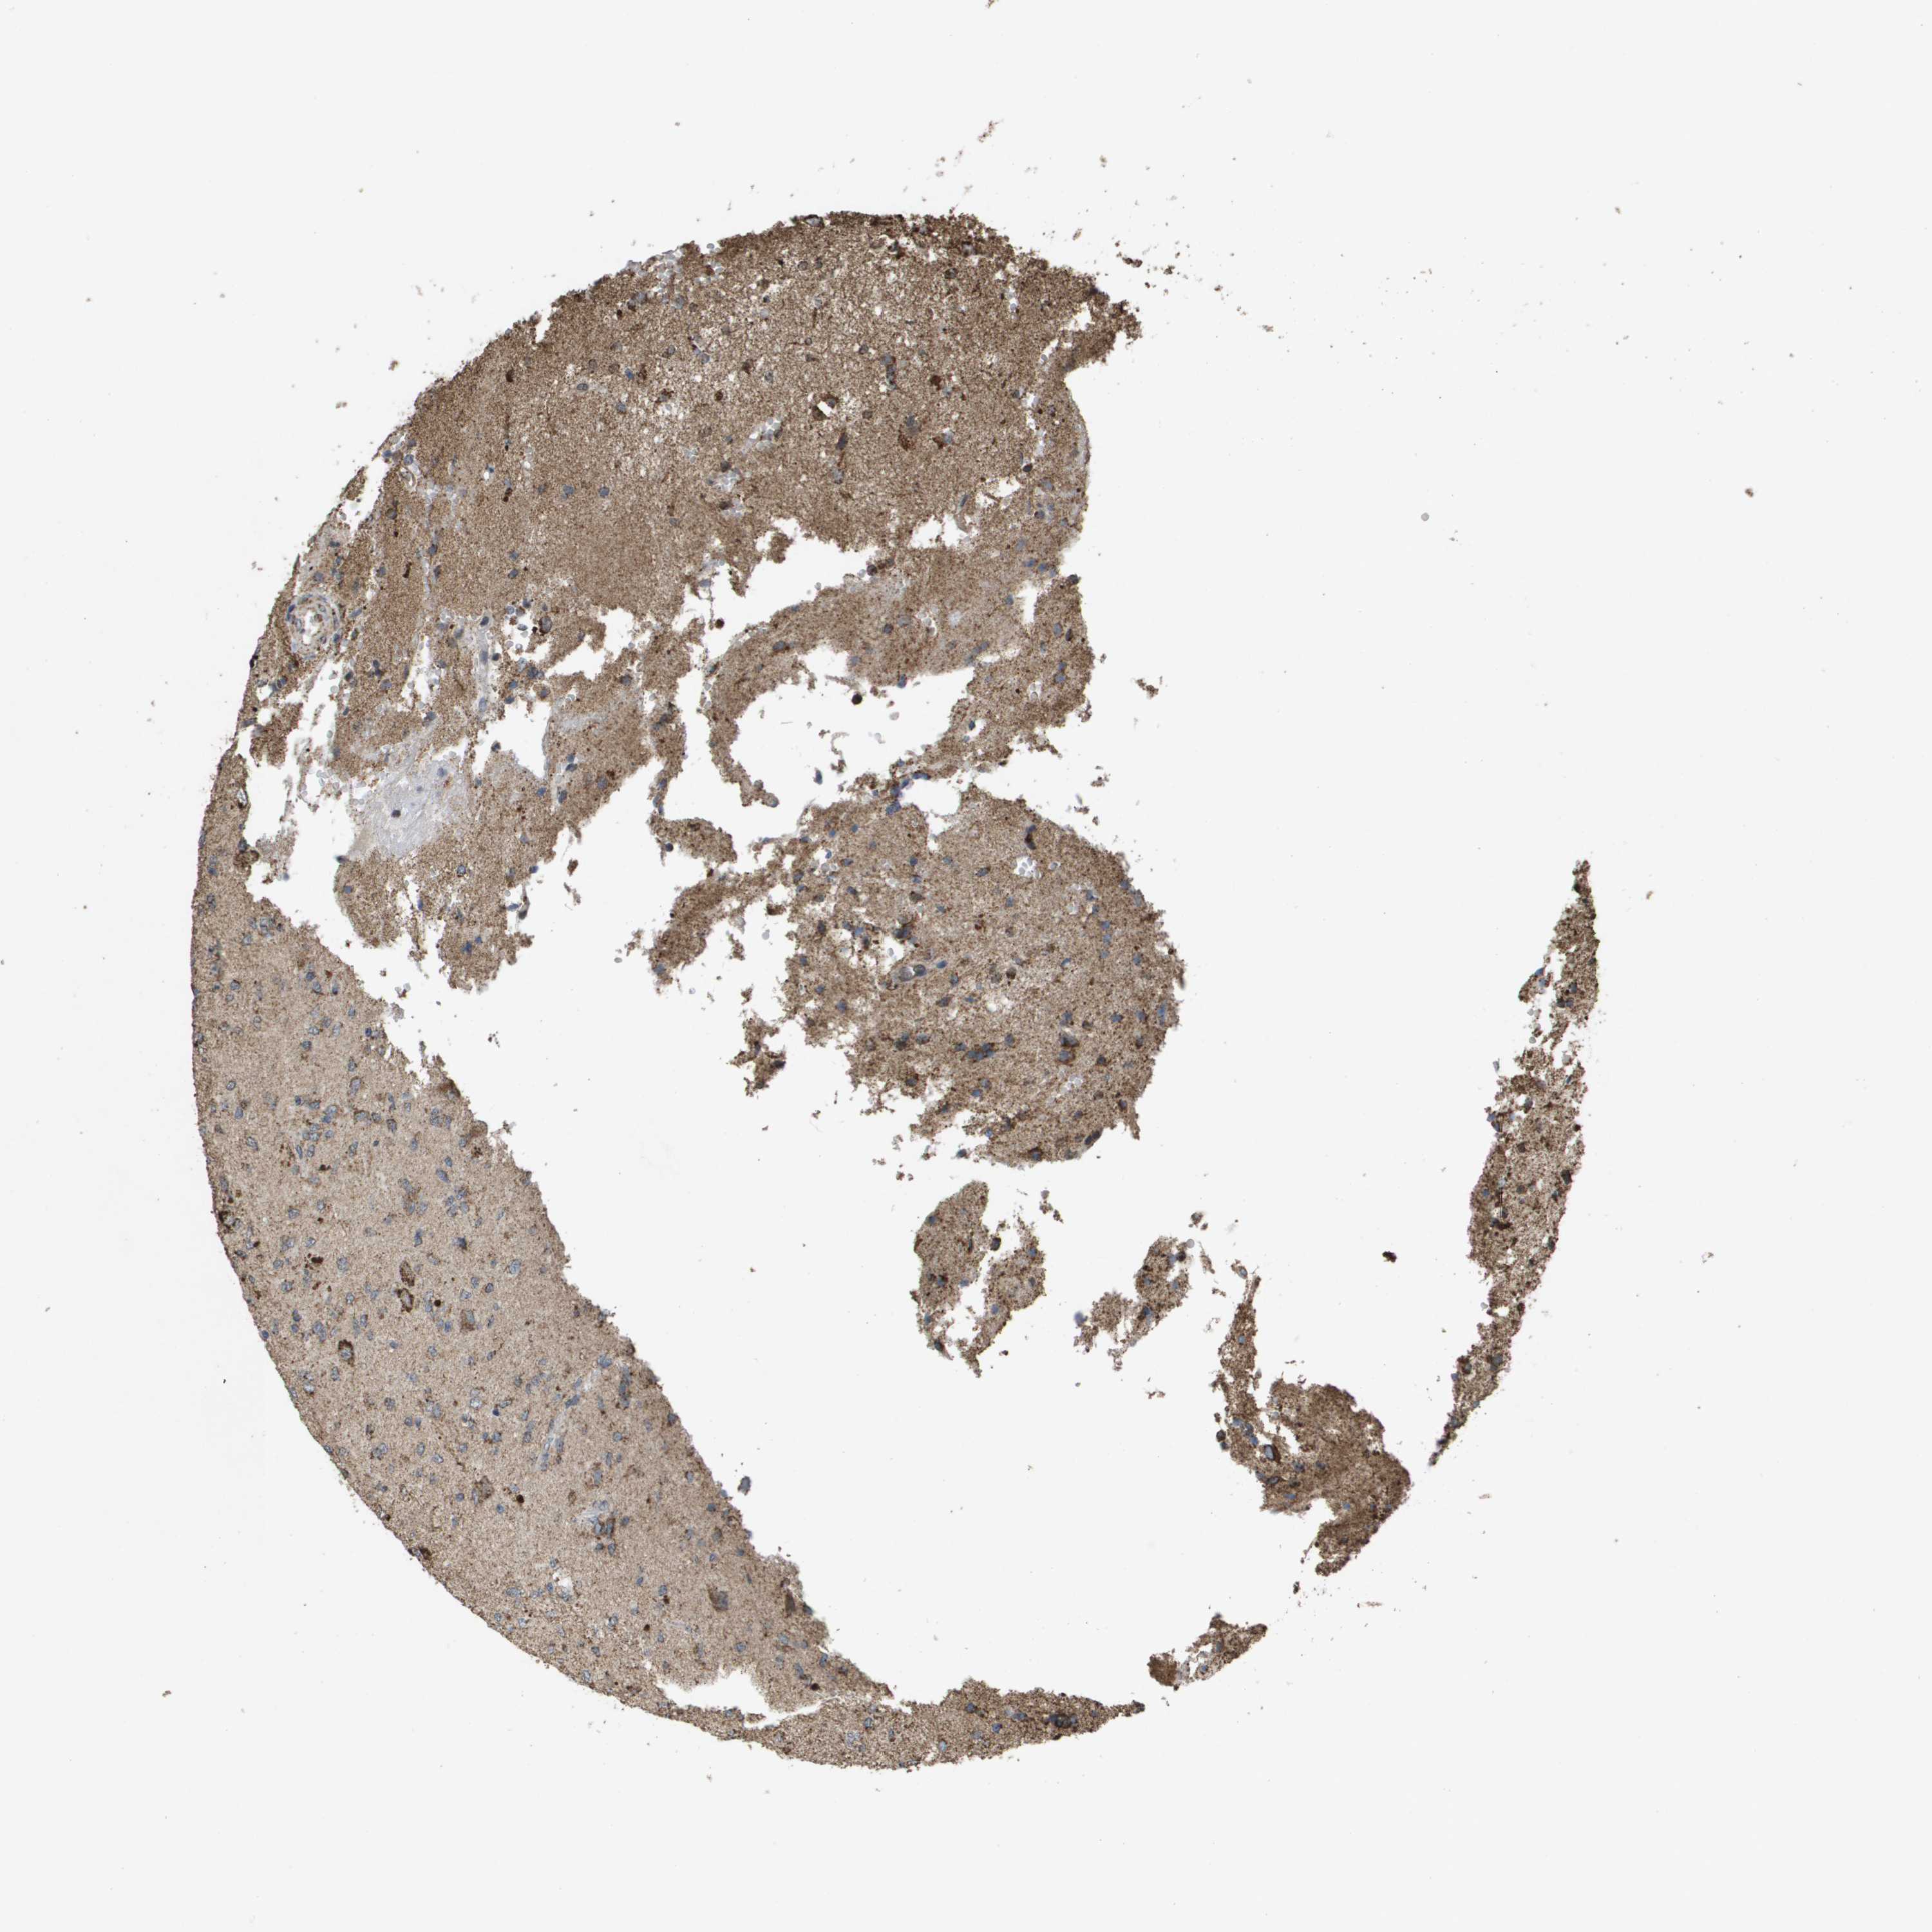

GLIOMA - Protein expressioni

A mouse-over function shows sample information and annotation data. Click on an image to view it in a full screen mode. Samples can be filtered based on level of antibody staining by selecting one or several of the following categories: high, medium, low and not detected. The assay and annotation is described here.

Note that samples used for immunohistochemistry by the Human Protein Atlas do not correspond to samples in the TCGA dataset.

Antibody stainingi

Antibody staining in the annotated cell types in the current human tissue is reported as not detected, low, medium, or high, based on conventional immunohistochemistry profiling in selected tissues. This score is based on the combination of the staining intensity and fraction of stained cells.

Each image is clickable and will lead to virtual microscopy that enables deeper exploration of all samples and also displays staining intensity scores, fraction scores and subcellular localization as well as patient and tissue information for each sample.

Antibody HPA038755

Antibody HPA048272

Antibody CAB017366

Staining

High

Medium

Low

Not detected

Intensity

Strong

Moderate

Weak

Negative

Quantity

>75%

75%-25%

<25%

None

Location

Nuclear

Cytoplasmic/membranous

Cytoplasmic/membranous,nuclear

Glioma, malignant, High grade

Glioma, malignant, Low grade

Glioblastoma, NOS